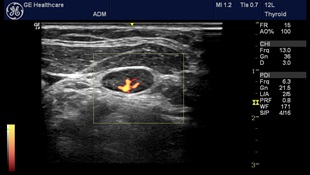

Tο ιατρείο μας παρέχει πλέον τη δυνατότητα εκτέλεσης κατ’ Οίκον όλων των εξετάσεων υπερηχογραφημάτων και triplex αγγείων. Με την καινούρια, φορητή και υπερσύγχρονη μονάδα υπερήχων NextGen LOGIQ e, General Electric (τελευταίας γενιάς) παρέχουμε την δυνατότητα για άμεσες λύσεις σε διαγνωστικά προβλήματα ακόμα και σε ασθενείς που δεν έχουν δυνατότητα μετακίνησης. Έτσι ο ασθενής και η οικογένειά του αποφεύγουν την ταλαιπωρία διακομιδής του σε νοσοκομεία ή διαγνωστικά κέντρα. Οι φορητοί υπερηχογράφοι μπορούν πλέον να εκτελέσουν όλες τις εξετάσεις, με τη βασική προϋπόθεση να είναι σύγχρονης κατασκευής. Η απουσία ακτινοβολίας και ο εύχρηστος τρόπος χρήσης καθιστούν την εξέταση πολύ προσιτή.